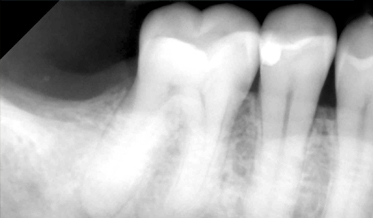

Use of Tuberosity Tissue Block for Tunneling Reconstruction of Class III Sockets With Simultaneous Implant Placement: A Case Report